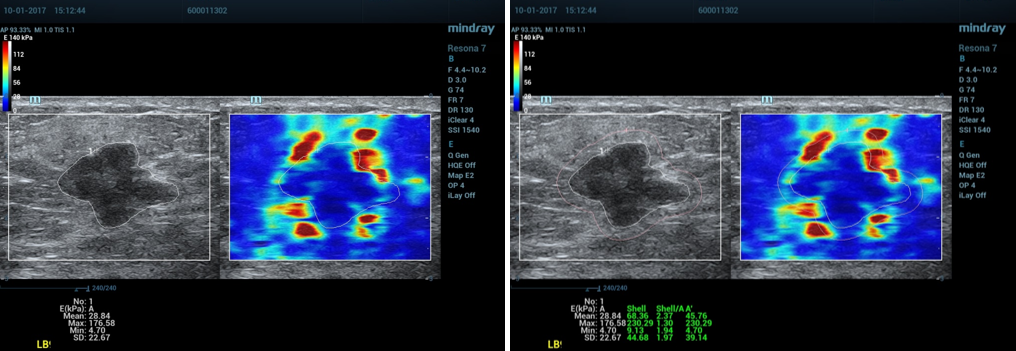

3、数据测量:

①按Measure按键

②选择测量杨氏弹性模量(E)(描记法)。

③描记肿块区域A后,系统自动计算出Emean、Emax、Emin和Esd。

④Shell 选择2mm,得出出肿块周边区域Shell的Emean、Emax、Emin和Esd。

4、正确操作示范:

①乳腺剪切波弹性成像